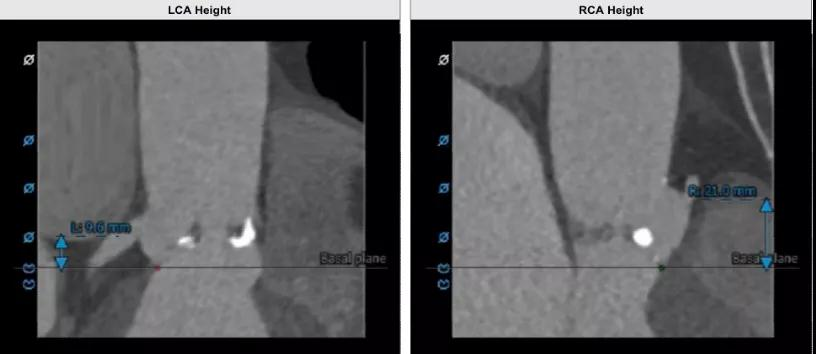

左冠脉开口高度9.6 mm,存在冠脉风险;右冠脉开口高度21.0 mm